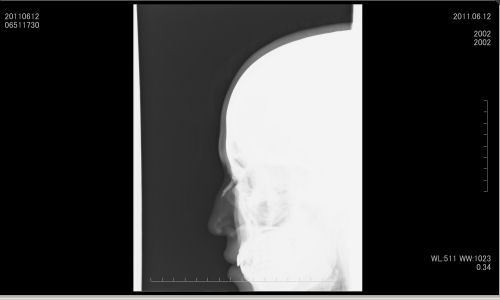

アイドルユニット「ぴゅあふる」の綾川小麦(あやかわ こむぎ)さんが、6月12日に行ったテレビ東京の音楽番組「月刊MelodiX!」の収録中、スタジオの溝に落下する事故で座骨や鼻骨を骨折し重傷を負っていたが、9月2日にライブハウス・渋谷DESEOのライブで元気に復帰した。

ライブ前に綾川小麦さんにお話しを伺うと「鼻骨の骨折は金具で折れた骨を持ち上げ治療を行いました。最初は5倍くらい腫れてびっくりしました。座骨の骨折は治療方法は無く、とにかく安静にすることを病院の先生に指示されました。」と事故後について振り返っていた。